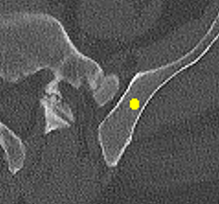

Figure 2: Qualitative results of bone lesion detection. Each column shows a cropped slice with the top row displaying ground-truth (green) and the bottom row showing nnUNet predictions (yellow). (a) shows a TP osteolytic lesion; (b) shows the prediction of a real osteoblastic lesion that was not prospectively marked as ground-truth (before review), and after GT review, it was correctly considered as ground-truth; (c) shows an osteolytic lesion not annotated in ground-truth before review and correctly marked afterwards. A FN adjacent to it is also shown. (d) shows a rare FP on the cortex of a rib.

Results. Qualitative and quantitative results of our model are presented in Fig. 2 and Table 1 respectively. Our model achieved a precision of 96.7% and a recall of 47.3% for detection of bone lesions (lytic, blastic, and mixed). We observed that the model was very confident in its predictions as demonstrated by the vast number of actual lesion predictions (TPs) compared against the FPs. Despite the high precision, the model was not very sensitive to the detection of bone lesions due to the large number of FNs.